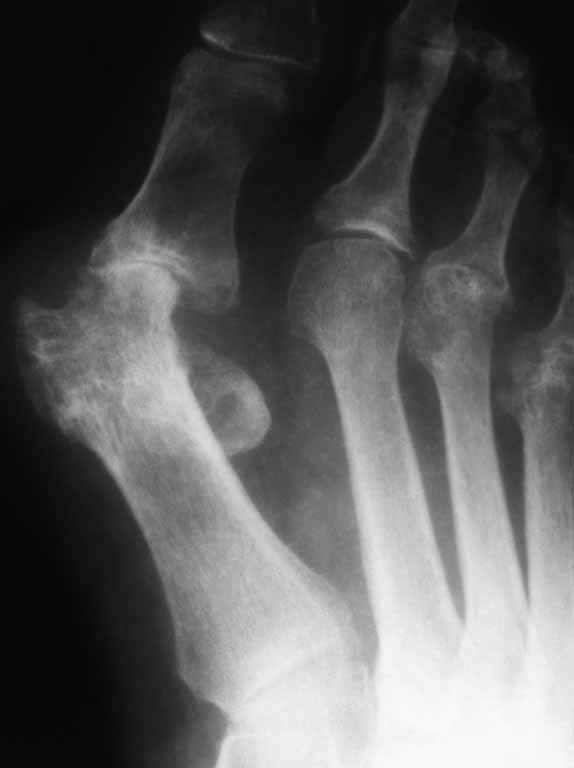

55 лет. Ревматоидный полиартрит.Артродез или протез ПФС?